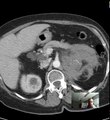

AIMMS LIBRARY CT SCAN COURSE VIDEO NO 13 CT Abdomen and Pelvis anatomy DISCUSSION